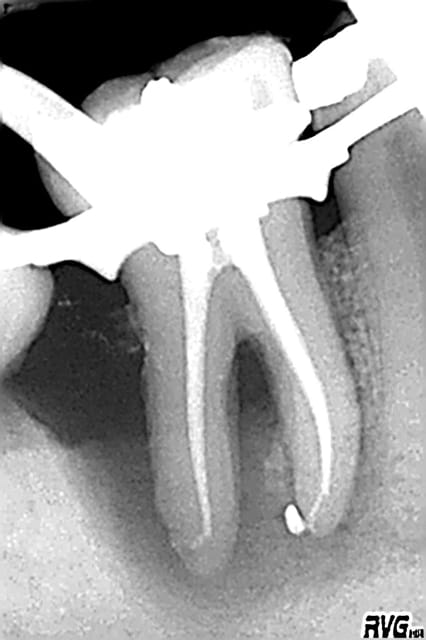

radio d'il y a 15 jours au vu de laquelle j'ai décollé, cureté, comblé

à suivre comme dirait je ne sais plus qui